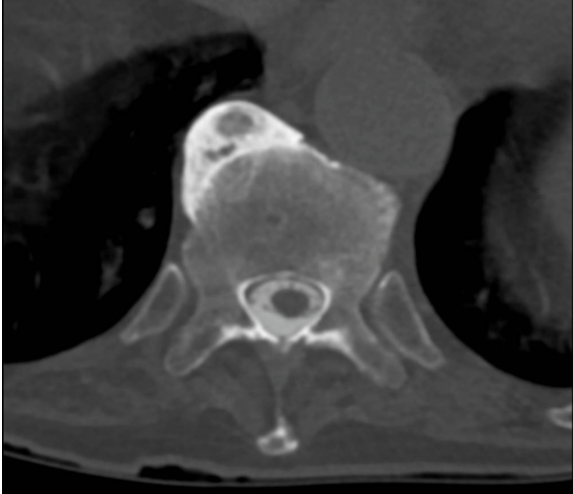

what are the radiographic findings of DISH

cf ankl spon